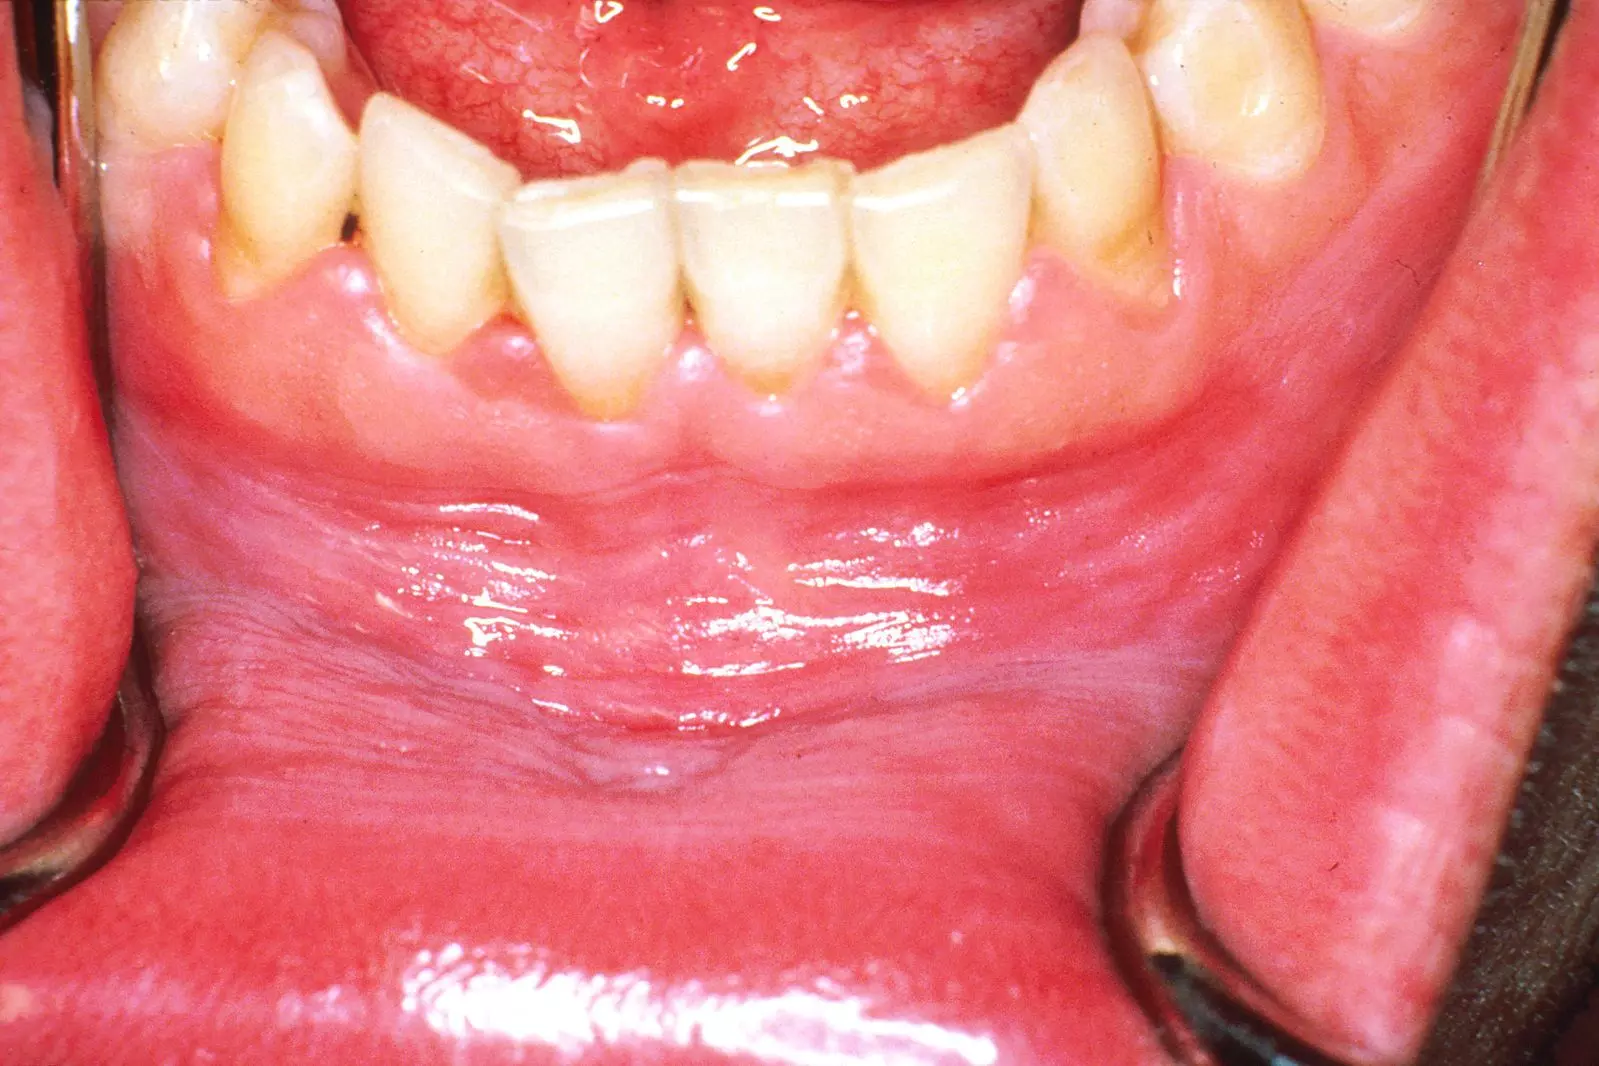

14. The Oral Cavity and Pharynx